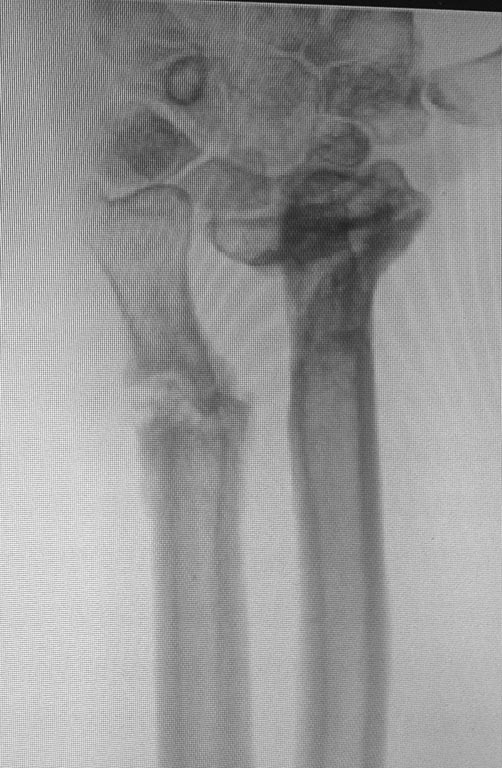

Последствие огнестрельного перелома костей предплечья

Пациент получил огнестрельное ранение левого предплечья с переломом обеих костей в нижней трети в августе 2014г. Первоначально лечился в аппарате Илизарова. Со слов пациента, в связи с развитием ИО в область проведения спиц аппарат демонтирован, продолжено лечение в повязке. В настоящее время в области левого предплечья множественные окрепшие послеоперационные рубцы, отмечается деформация в виде выстояния головки локтевой кости, формирования гипертрофической костной мозоли лучевой кости. Рентгенограммы прилагаю.

Основная жалоба - ограничение супинации, которое мешает выполнять работу.